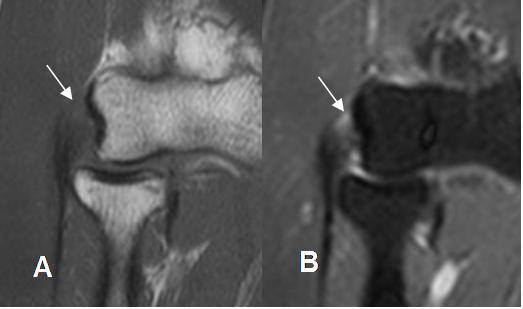

Fig 49 E. Epicondilitis lateral.

A: RM T1 coronal y B: RM coronal STIR. Tendon hipointenso en T1 e hiperintenso en STIR a nivel de su origen, por inflamación.